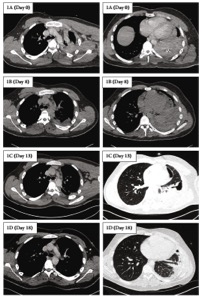

体格检查显示,患者心率为93次/min,血压为106/55 mmHg,呼吸频率34次/min,补充氧气下,氧饱和度97% L/min。ICD已引流1800ml血液 。血液检查显示血红蛋白为140g/L(正常135-172g/L),血小板263×10^9(150-370×10^9),凝血酶原时间13.4 s(正常10.8-13.3s),活化部分凝血活酶时间24.7 s(正常28.2-36.6 s),纤维蛋白原为2.62 g/L(1.46-3.33 g/L)。肾功能和肝功能检查均在正常范围内。胸部CT显示左侧血胸轻微缩小,无活动性出血迹象(图1a)。ICD被放大到32Fr以促进凝块清除,并给予预防性静脉注射阿莫西拉联合。不需要进一步的血液制品,患者得到保守治疗。

三天后,在最小输出量和胸部X线(CXR)显示少量残留积液后24小时取出ICD。一天后,患者再次发烧,炎症标志物升高。重复胸部CT显示中等容量血胸(图1b)。胸腔超声(TUS)发现有组织的胸膜腔,类似血肿,胸腔积液极少。考虑到残留血胸内脓胸的演变,将阿莫西拉联合夫改为哌拉西林/他唑巴坦,并在超声引导下将12FrICD插入复杂胸腔积液。最初排出了300 ml红棕色液体(降解的血红蛋白),胸腔内注射10 mL生理盐水稀释的10 mg阿替普酶之后又排出800 mL。第二天的CXR显示胸腔积液的体积增大。

图1. 连续轴位胸部计算机断层扫描(CT)显示左侧血胸随时间缩小。左侧和右侧的图像分别代表在隆凸和肺底水平拍摄的CT图片。第0天为入院日

然而,TUS展示出自由流动的流体量少。加上稳定的血红蛋白和最小的ICD输出量,认为这种变化更可能是由于脓胸的演变而不是复发性胸膜出血。再次给予两剂胸腔内纤溶治疗(10mg 阿替普酶和5 mg阿法链道酶),导致进一步引流2000mL红棕色液体。随后的胸部CT显示肺萎陷(图1c)。同时,胸腔积液以渗出物形式返流,pH、镜检及培养均无感染迹象。

由于患者拒绝手术,因此将第二个ICD插入基底部,胸腔内再次给予10mg阿替普酶,来尝试清除胸膜腔并破坏胸膜粘连。四天后进行的胸部CT显示有显著改善,残余液体最少,肺萎陷几乎完全再扩张(图1d)。两个ICD都被移除,患者第二天出院。整个住院期间血红蛋白保持稳定,无需输血。在两周后的随访中,患者完全康复,CXR显示左肋膈角的钝化程度最小(图2)。